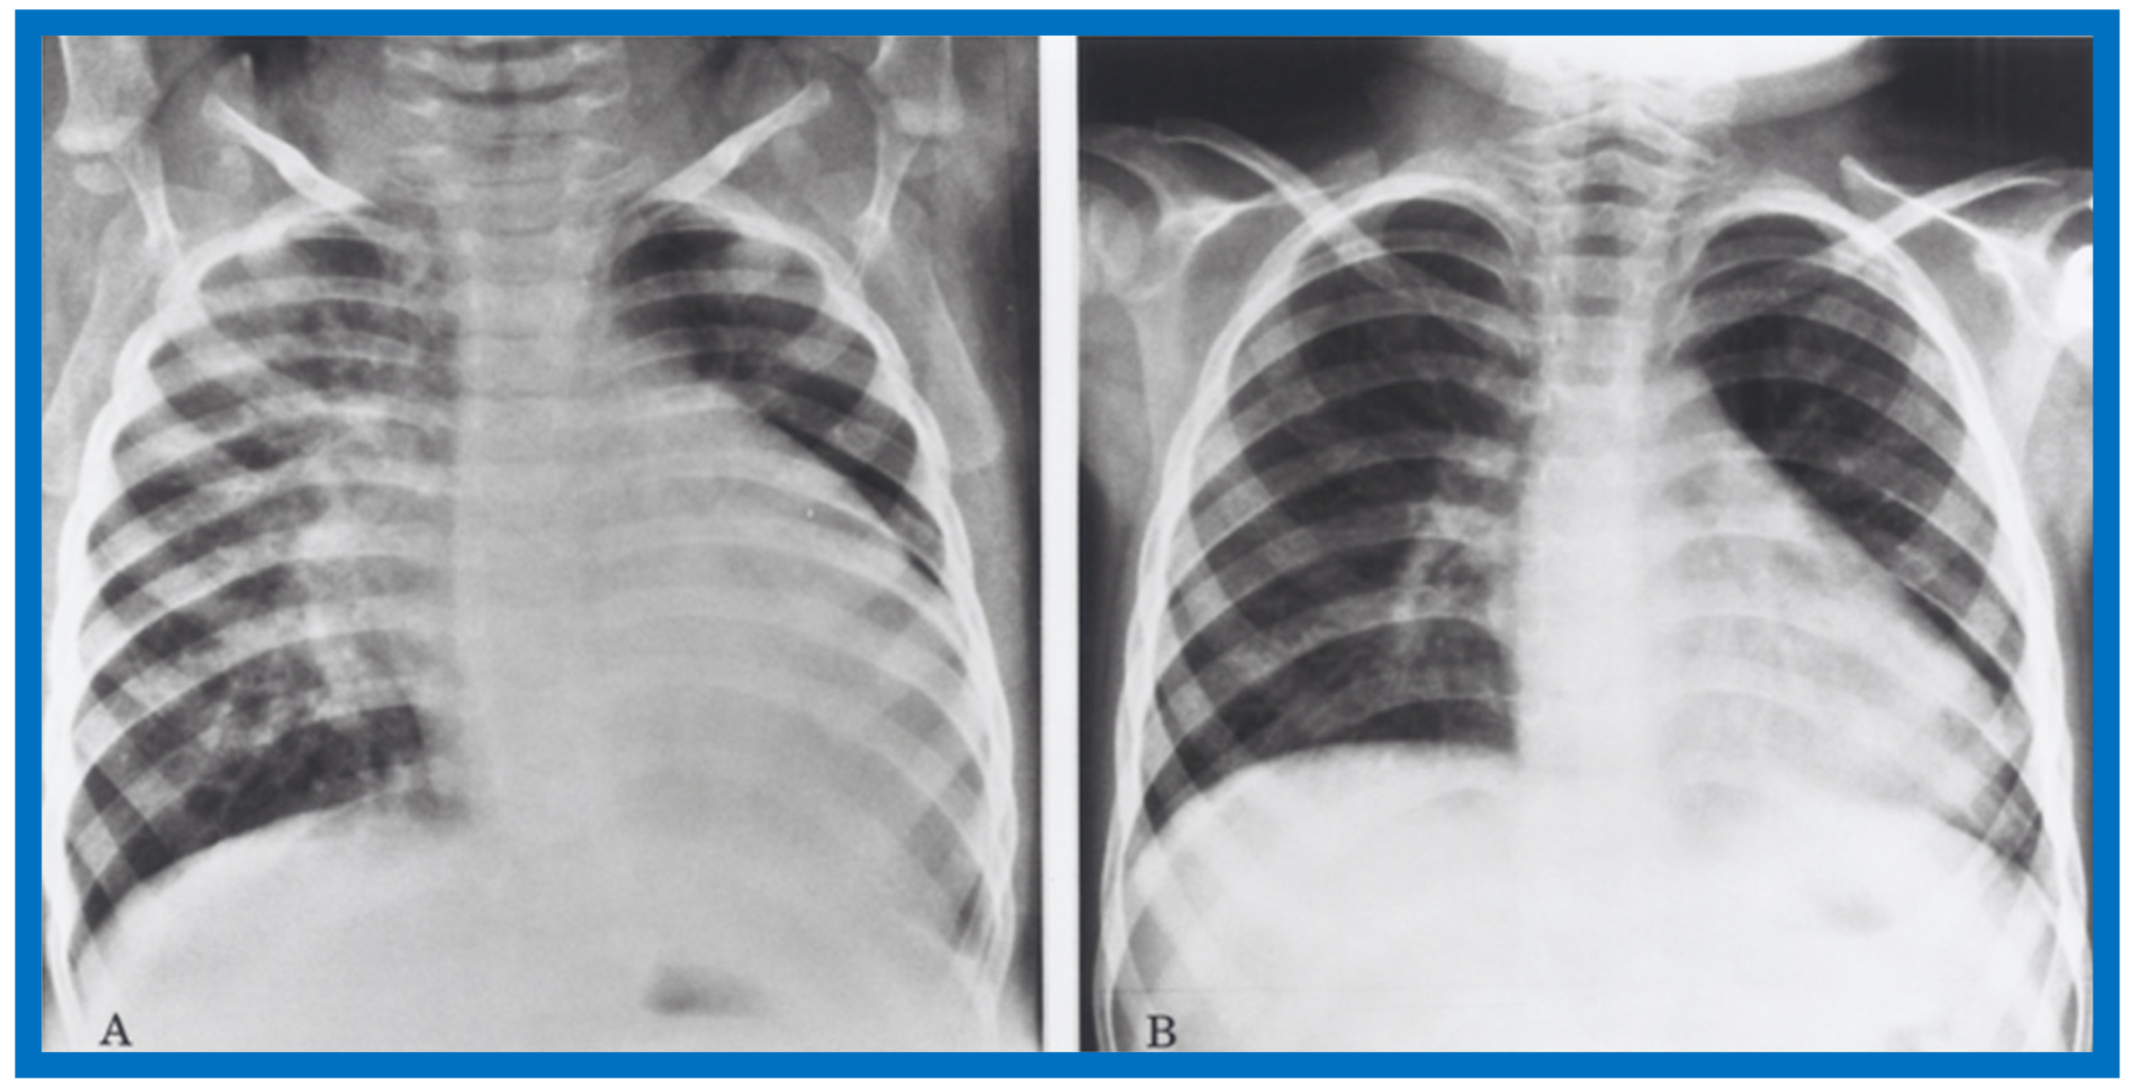

Examples of improvement in LV dimension on echo studies are shown in Figure 40 and Figure 41. The cardiac size and pulmonary venous congestion on chest roentgenograms improved in the hydralazine group (Figure 42 and Figure 43). No significant changes in any of these parameters occurred in the control group.

Figure 42.

Antero-posterior view of chest x-rays prior to (A) and following (B) hydralazine therapy. Moderate cardiomegaly and pulmonary venous congestion were seen prior to therapy (A) which improved remarkably after therapy (B).

Figure 43.

Antero-posterior view of chest x-rays prior to (A) and following (B) hydralazine therapy from a different infant. Moderate cardiomegaly with pulmonary venous congestion was seen prior to therapy (A) which improved remarkably after therapy (B), similar to that seen in Figure 42.

While this was a prospective study, we did not use concurrent controls, nor was this a double-blind randomized study with placebo administration in the control group. Consequently, we suggested a double-blind randomized study to confirm our findings. We stated that hydralazine does not alter the basic cardiac disease, but by improving the cardiac output, prolongs the patients’ life, giving an opportunity for recovery of cardiac function and spontaneous improvement, should that be the natural history of disease. We concluded that hydralazine therapy is a valuable addition in the management of PMD in infants and children [12]. Subsequent to the initiation of our study, afterload reducing, angiotensin-converting enzyme (ACE) inhibitors came into vogue and may be considered superior to hydralazine.